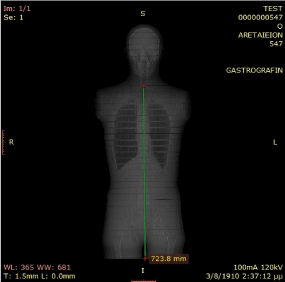

All patients were positioned supine, head first, with the arms above their head. Scan lengths varied between 1.05 – 1.54 m, measuring from the top of the head to the level beneath the knees (Figures 1 and 2).

Figure 1. CTDIvol and the DLP values are displayed on the CT screen, useful in evaluation of absorbed dose delivered per MDCT scan performed on the Philips CT Brilliance 16 scanner in our Radiology department.